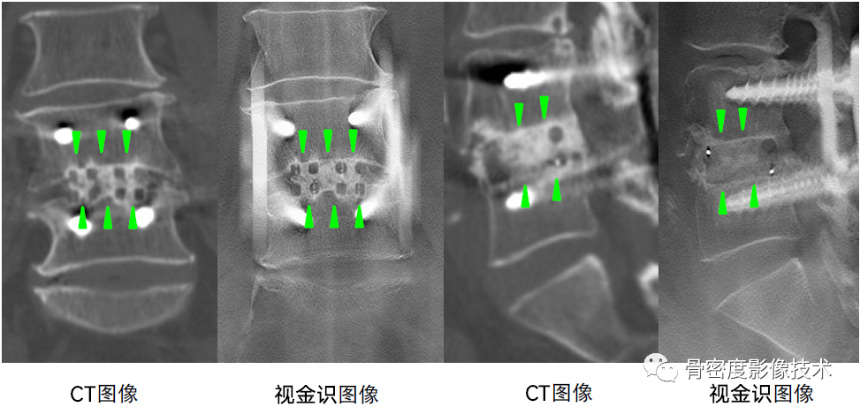

视金识功能

可以适用于金属植入物分辨

图4 腰椎骨密度术前评估联合椎间盘置换及内固定术后评价